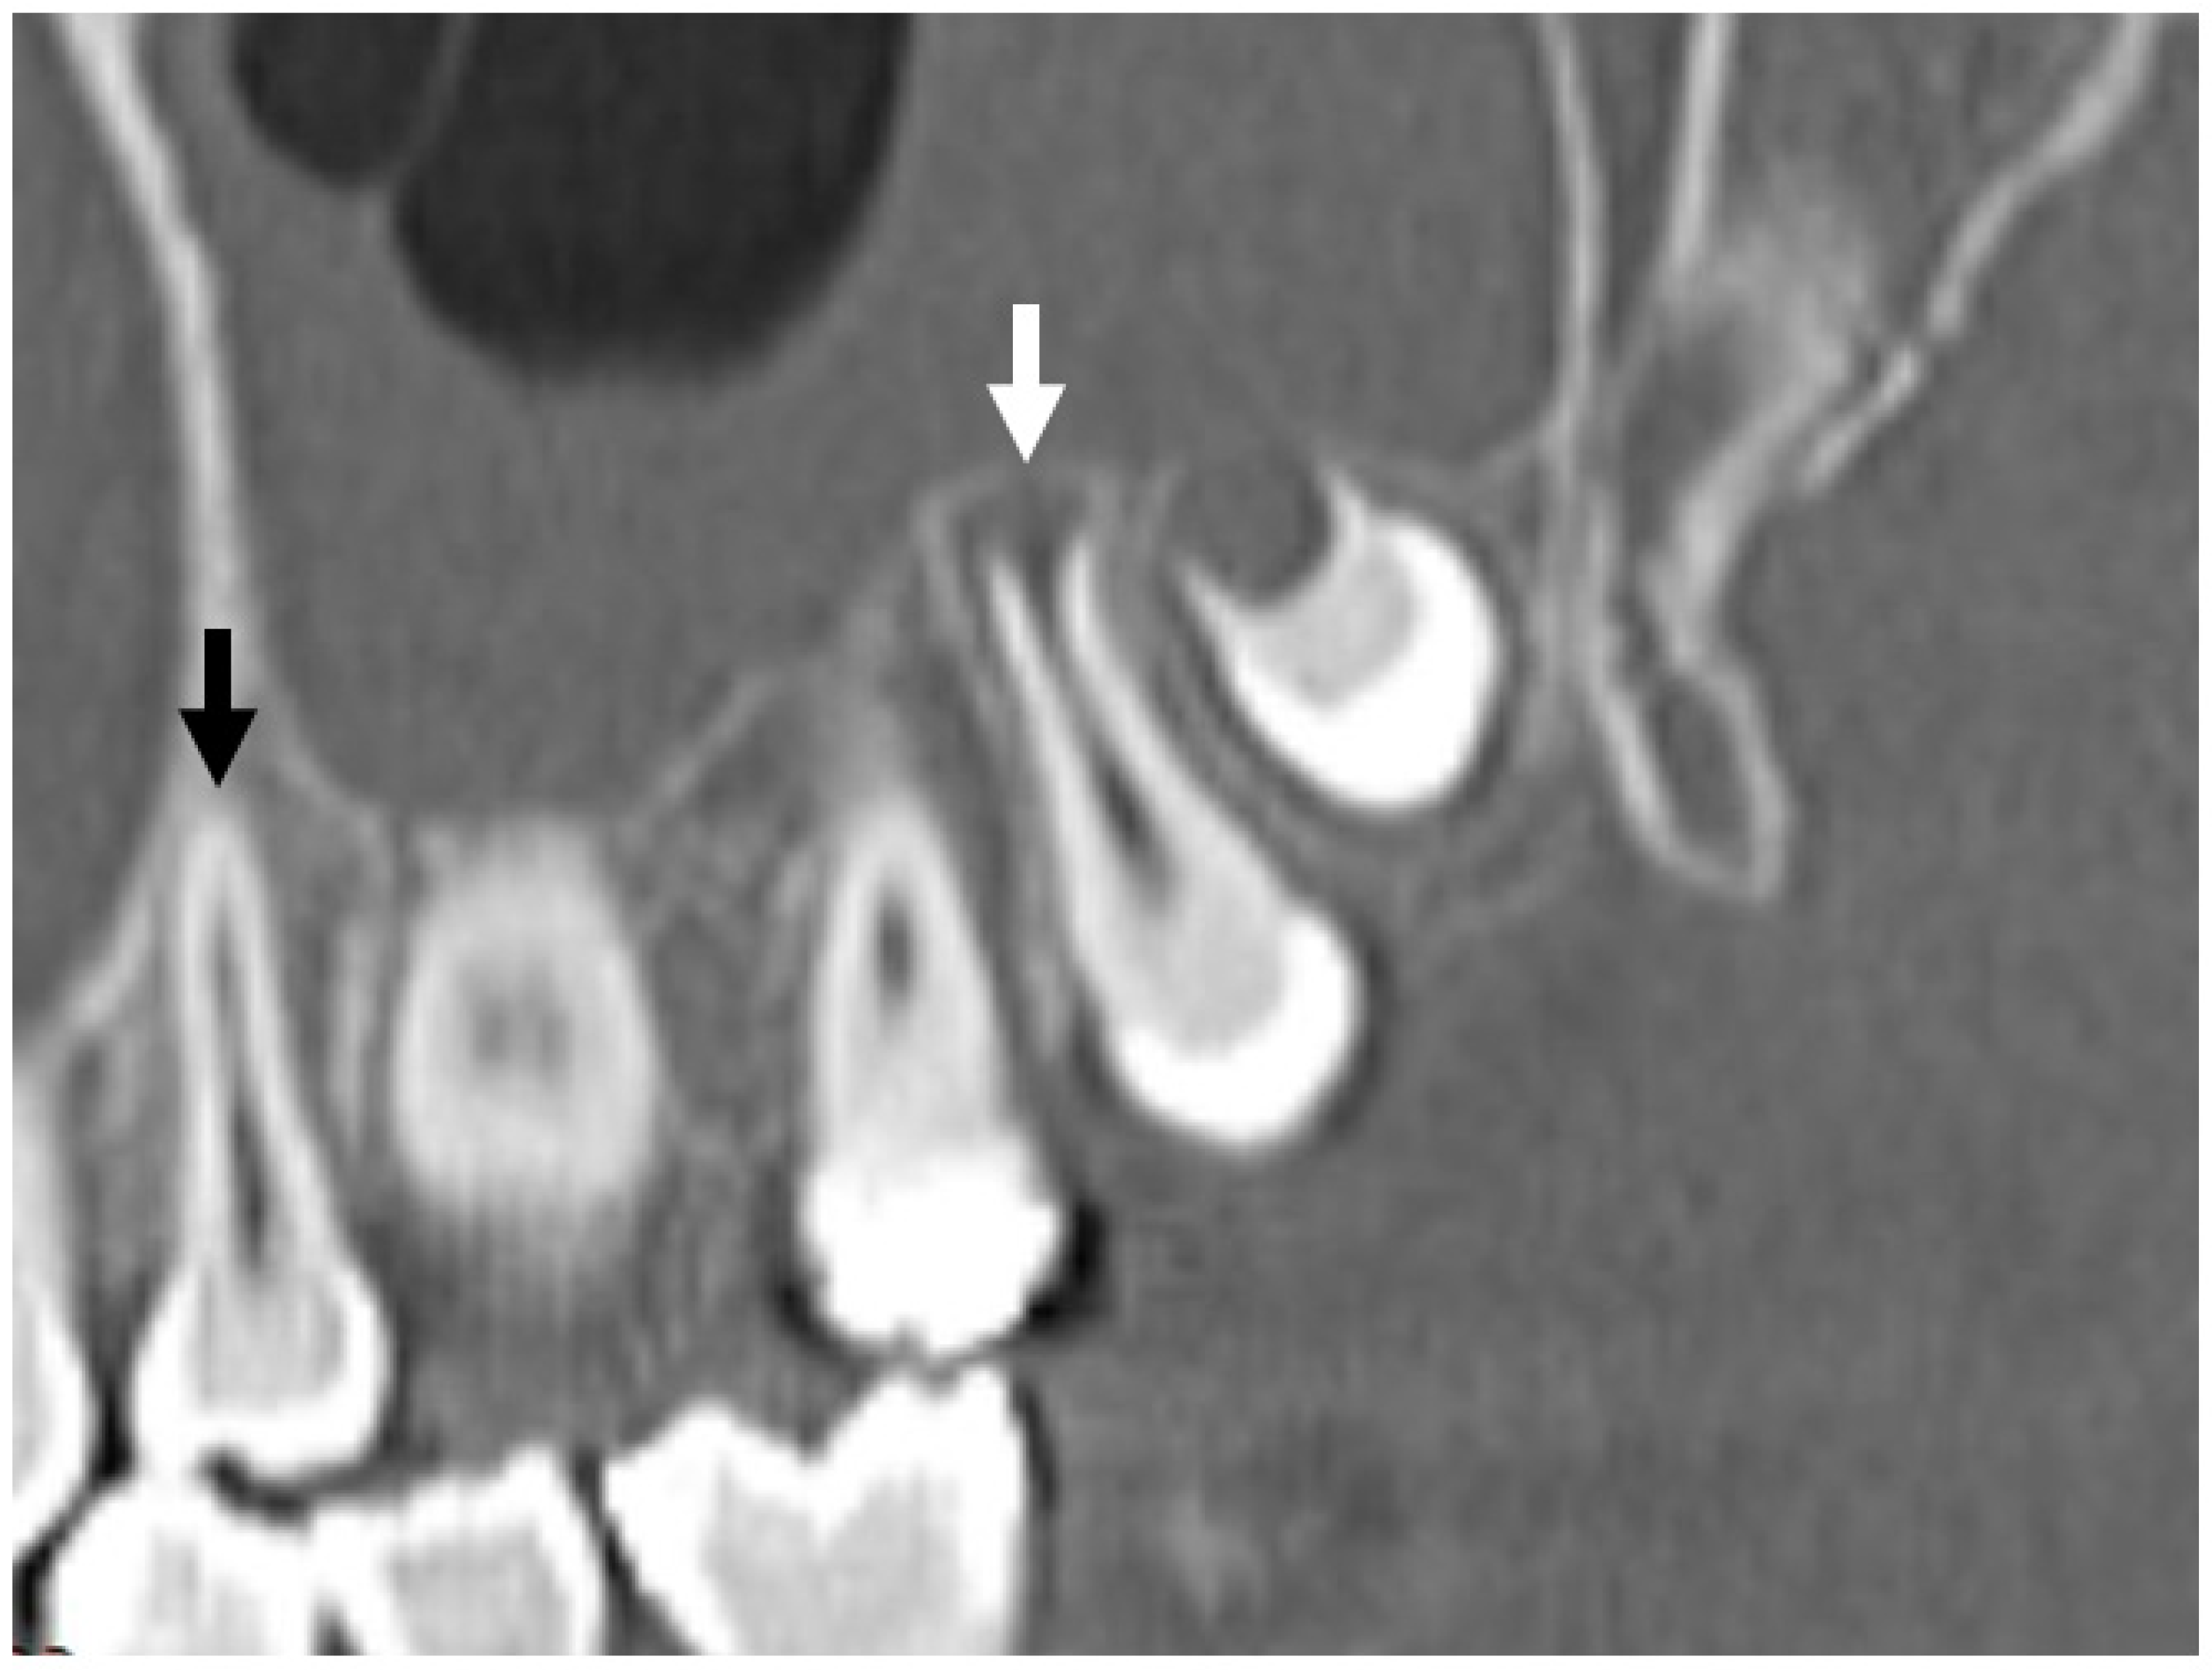

2. Materials and Methods

3. Results

3.5.2. Dental Decay Radiologic Correlations

3.5.4. Periodontal Disease Radiologic Correlations